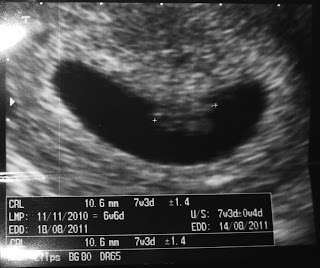

Nyt sitten kuuluu sanoa "ooooo, onpa suloinen!". Möykyn sykkivän kiehtova olemus ei taida nyt aivan näistä vanhan teknologian potrettikuvista välittyä, mutta kuvitelkaa se potkuhousuissa. ;)

Tässä hän on: pötkylä kaksinkerroin. Nuo plussanmuotoiset osoittimet mittaavat pääperämittaa (CRL) eli tästä voinee päätellä, että ensimmäisessä kuvassa Möykyn pää on vasemmalla ja toisessa oikealla.

Tässä kolmannessa kuvassa on mitattu Möykyn sykettä viivojen muodossa. Tulos oli 119 lyöntiä minuutissa, mikä on kuulemma tämänikäiselle alkiolle normaali syke.

Alan onneksi olla jo niin loistava ultraäänikuvien tulkitsija, ettei tarvinnut sitten jännittää enää yhtään sekuntia kauempaa. Näin sen heti: sikiöpussissa oli joku ja sillä oli yhtä kova syke kuin minulla. Jee! (Noin niin kuin lievästi ilmaistuna.) Eihän se joku oikein miltään vielä näyttänyt - semmoinen epämääräinen, kippurainen, sykkivä möykky. Mutta lääkärin mukaan siitä yhdeksän millin möykystä tulee meille 95 prosentin todennäköisyydellä vauva. Se on jo varsin mukava todennäköisyys. :) Tästä on hyvä lähteä hyppelemään seuraavia odotusajan tasoja eteenpäin.

Ainut vähän outo juttu oli, että se meidän möykky oli hiukan isompi kuin mitä viikot antaisivat olettaa. Lääkäri mittasi sen iäksi moneen eri kertaan 7+1, vaikka se on ihan maksimissaan 6+6-ikäinen, luultavasti vielä päivän pari nuorempi. No, parempihan se on noin päin. Ja luultavasti kyse on vain siitä, että se ultranäkymä on niin todella epämääräinen. Laitan teille kuvia illalla - näette sitten itse.